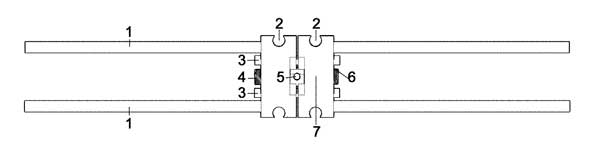

Dr. Kanaan redesigned the SME to fit narrower palates with a safety release mechanism. He filed his invention with the United States Patent Office on Oct 10th, 2016 under Application US15/333,531 “Safety release orthodontic skeletal expander using mini-implants” (REF).

His expander comes in two sizes: 7 mm and 9 mm. However, in extremely narrow cases, Dr. Kanaan will custom-make a surgical expander to fit the patient's mouth. A cone-beam computed tomography might need to measure the exact width of the maxilla.